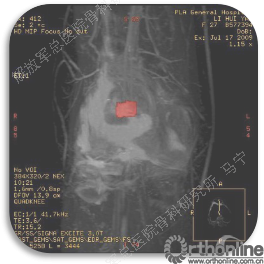

首先经过核磁的检查、评估,初步确定软骨损伤范围,利用T2maping检测序列对软骨的信号区分。图中我们可以看到软骨损伤的范围,并通过计算机计算出大概的面积。

姜**:男,33岁 ,双膝疼痛,活动受限1年,曾经打过玻璃酸钠,效果都不理想,来我院行软骨修补术,MRI显示髌骨软骨下骨增生明显,并开始磨损滑车。

术后3个月在当地医院复查MRI,软骨补片与正常软骨还存在GAP现象,冠状位隐约还能看见周围的轮廓。

术后6个月复查MRI,软骨修复的已经具备一定的厚度,软骨下骨没有明显水肿。增生的软骨下骨被去除后没有再进一步磨损滑车软骨。